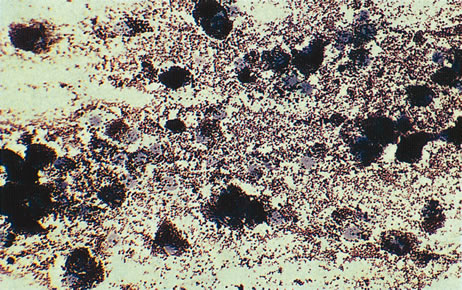

Figure 16 shows a case of what clinically and ultrasonographically appeared to be a uveal melanoma. The FNAB specimen revealed a cellular pattern that was diagnostic of a primary carcinoid (Fig. 17), and the patient responded dramatically with 40 gray of photon radiation. Figure 18 shows the FNAB cytopathology of a typical epithelioid choroidal melanoma; in contrast, a smear of a spindle cell tumor has spindle-shaped cytoplasm and smaller nuclei. Figure 19 shows a benign pigmented mass, such as a retinal pigment epithelial proliferation or a melanocytoma. In contrast to a melanoma, this type of mass has much larger pigment granules and benign cytomorphologic detail. In addition to standard cytopathologic FNAB evaluation, aspirated material may be used for several molecular biology studies (e.g., fluorescence in situ hybridization, comparative genomic hybridization), flow cytometry, special stains, tissue culture, and ultrastructural analyses.

Fig. 17. Fine-needle aspiration biopsy of the patient in Figure 16 shows that the lesion is a primary carcinoid.

Fig. 18. Cytopathology from a fine-needle aspiration biopsy demonstrates an epithelioid melanoma.

Fig. 19. Fine-needle biopsy from a benign melanocytoma. In contrast to a uveal melanoma, a benign melanocytoma has pigment granules that are much larger. Its nuclear detail is also bland and lacking nucleoli.